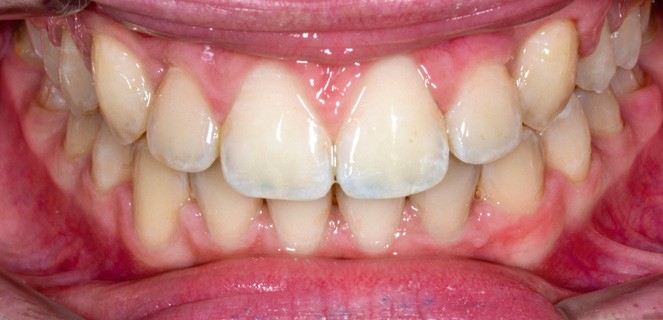

Un arc acier .019 x .025 est inséré à l’arcade maxillaire et les finitions sont réalisées sur des arcs en TMA .017 x .025.

L’appareil est déposé après la mise en place de contentions collées de 12 à 22 et de 33 à 43 avec le port nocturne d’une plaque de Hawley à l’arcade maxillaire. Le temps de traitement actif a été de 41 mois.